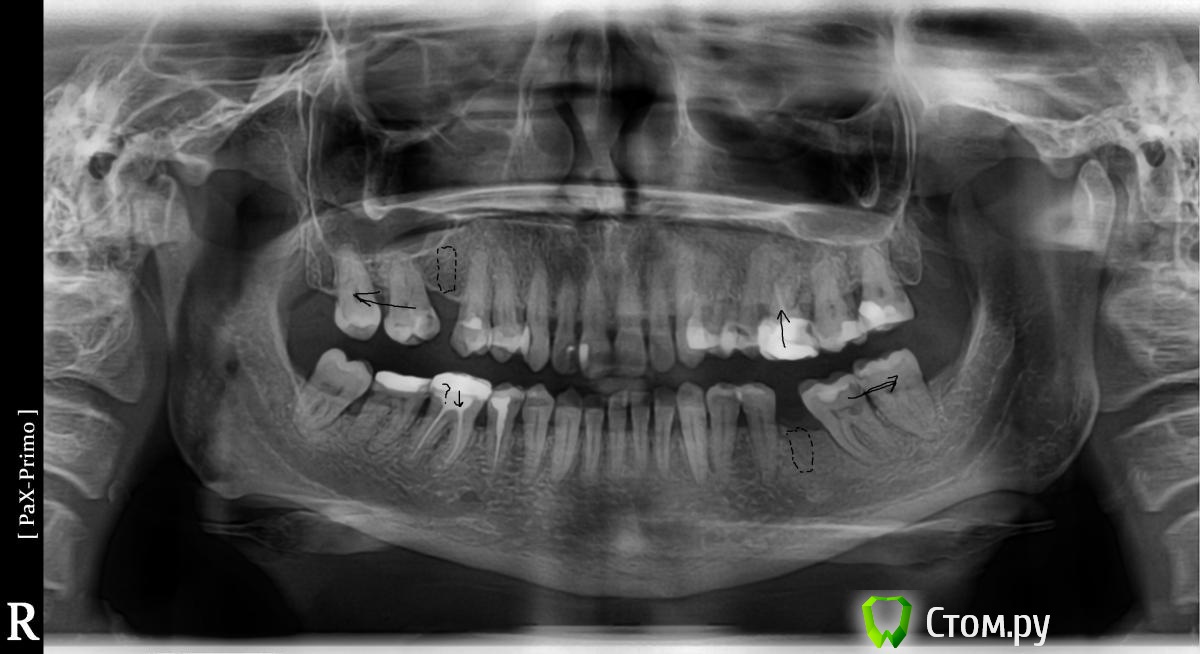

artem29 Опубликовано 12 декабря, 2013 Поделиться Опубликовано 12 декабря, 2013 всем привет!!! Я хирург. В клинике планируется работа с микровинтами. Пациентка брекетсистему "носить" не планирует (остановились на локальном решении задач) Задача: Ортопеду необходимо освободить место для будущих искусственных зубов 1.6 и 3.6. Для этого пациентка (50 лет), отправляется на консультацию к ортодонту для решения вопроса у дистализации зубов 1.7 и 3.7. В данном клиническом случае по хирургическим показаниям зубы мудрости планировались на удаление, сейчас добавились и ортодонтические, как я понимаю для дистализации 1.7 и 3.7 надо удалить 1.8 и 3.8. Ортодонт на микровинтах не работала, но мотивация есть. С ортодонтом видемся редко, у нас в клинике только консультативны прием, обсудить что-то вместе крайне редко получается (тем более провести совместную консультацию), меня как хирурга ортопед попросил посмотреть снимки, определить свой (хирургический объем работы). Изучив информацию (литературу и форумы) я пришел к такому варианту действий,чтобы дистализировать 1.7 необходимо удалить 1.8 установить микровинт вестибулярно между корнями 1.4 и 1.3 (т.к. там больше места чем между 1.5 и 1.4) к 1.7 фиксировать брекет-замок, между ними установить пружину, зуб 1.7 дистализируется. для дистализации 3.7 необходимо удалить 3.8, оценить состояние костной ткани, возможно установить микровинт дистально одномоментно с удалением 3.8 если межокклюзионной высоты для головки микровинта будет достаточно. Вторым путем (при отсутствии состоятельной костной опоры в момент удаления 3.8 является установка микровинта между корнями зубов 3.4 и 3.5, брекет на зуба 3.7 + пружина. есть ещё один вариант. удалить 1.8 и 3.8, дождаться пока пройдет формирование костной ткани (сделать КТ через 3 месяца) установить микровинты в уже сформированную кость Вопросы: 1. кто определяет место установки микровинтов, ортодонт или хирург? 2. если изначально определяет место установки винтов хирург, то какие зоны необходимо в данной случае взять за костные опоры (куда ставить установить микровинты) к какие ортодонтические конструкции будут? 3. оптимально ли в данной ситуации дистализировать с помощью микровинтов, или возможны другие варианты Ссылка на комментарий

Toothfairy Опубликовано 12 декабря, 2013 Поделиться Опубликовано 12 декабря, 2013 Добрый вечер. Место установки минивинта определяет ортодонт. Хирург оценивает костную ткань в планируемом месте установки.Для дистализации зуба 1.7 лучше установить минивинт в область бугра верхней челюсти после удаления зуба 1.8 , а для дистализации 3.7- в ретромолярную область, предварительно удалив 3.8. После удаления восьмерок рекомендуют выждать 7-8 мес, я ставила через 6 , все было хорошо. Ссылка на комментарий

M@estro Опубликовано 12 декабря, 2013 Поделиться Опубликовано 12 декабря, 2013 Интрузию 4.6 и 2.6 я просить бы не стал. (а 2.6 вообще под вопросом на выход). Думаю, дистализацию в первом квадранте можно выполнить "пружинкой" ,оттолкнувшись от премоляров,хотя утверждать не берусь. P.s. Гигиена - кошмар. Ссылка на комментарий

Ayrat_zub Опубликовано 12 декабря, 2013 Поделиться Опубликовано 12 декабря, 2013 (изменено) конкретно всем привет!!! Я хирург. В клинике планируется работа с микровинтами. Пациентка брекетсистему "носить" не планирует (остановились на локальном решении задач) Задача: Ортопеду необходимо освободить место для будущих искусственных зубов 1.6 и 3.6. Для этого пациентка (50 лет), отправляется на консультацию к ортодонту для решения вопроса у дистализации зубов 1.7 и 3.7. В данном клиническом случае по хирургическим показаниям зубы мудрости планировались на удаление, сейчас добавились и ортодонтические, как я понимаю для дистализации 1.7 и 3.7 надо удалить 1.8 и 3.8. Ортодонт на микровинтах не работала, но мотивация есть. С ортодонтом видемся редко, у нас в клинике только консультативны прием, обсудить что-то вместе крайне редко получается (тем более провести совместную консультацию), меня как хирурга ортопед попросил посмотреть снимки, определить свой (хирургический объем работы). Изучив информацию (литературу и форумы) я пришел к такому варианту действий,чтобы дистализировать 1.7 необходимо удалить 1.8 установить микровинт вестибулярно между корнями 1.4 и 1.3 (т.к. там больше места чем между 1.5 и 1.4) к 1.7 фиксировать брекет-замок, между ними установить пружину, зуб 1.7 дистализируется. для дистализации 3.7 необходимо удалить 3.8, оценить состояние костной ткани, возможно установить микровинт дистально одномоментно с удалением 3.8 если межокклюзионной высоты для головки микровинта будет достаточно. Вторым путем (при отсутствии состоятельной костной опоры в момент удаления 3.8 является установка микровинта между корнями зубов 3.4 и 3.5, брекет на зуба 3.7 + пружина. есть ещё один вариант. удалить 1.8 и 3.8, дождаться пока пройдет формирование костной ткани (сделать КТ через 3 месяца) установить микровинты в уже сформированную кость Вопросы: 1. кто определяет место установки микровинтов, ортодонт или хирург? 2. если изначально определяет место установки винтов хирург, то какие зоны необходимо в данной случае взять за костные опоры (куда ставить установить микровинты) к какие ортодонтические конструкции будут? 3. оптимально ли в данной ситуации дистализировать с помощью микровинтов, или возможны другие вариантыконкретно в этом случае можно обойтись без миниимплантов, имхо) с помощью кантилеверов(специальных пружинок)в первом квадрате- тоже мезиальный наклон моляров насколько вижу всего лишь, тоже провести апрайт, и освободится место) по моделям проще просчитать) положение минимплантов- компромисс между желанием ортодонта, и возможностями хирурга) Изменено 12 декабря, 2013 пользователем Ayrat_zub Ссылка на комментарий